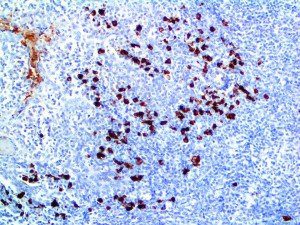

It is the ICU physician who is most likely to witness one of the deadliest manifestations of the abnormal immunological response, the cytokine storm syndrome (CSS). This response is also referred to by some as the cytokine release syndrome (CRS). CSS is characterized by continuous activation and expansion of macrophage and lymphocyte populations, which secrete large amounts of cytokines, causing the cytokine storm. This massive cytokine release is akin to hemophagocytic lymphohistiocytosis (HLH) disease, a syndrome characterized by initial unchecked and persistent activation of cytotoxic T lymphocytes and NK cells.

Clinical and laboratory manifestations of HLH include fever, enlarged liver and/or spleen, neurologic dysfunction, coagulopathy, liver dysfunction, cytopenias (i.e., low levels of erythrocytes, leukocytes, and/or platelets), hypertriglyceridemia, hyperferritinemia, hemophagocytosis, and eventually diminished NK cell activity as the immune system becomes progressively paralyzed. HLH can be familial (primary HLH) or secondary to another disease process (sHLH), such as rheumatic disease, in which it is referred to as macrophage activation syndrome (MAS, characterized by elevated ferritin).